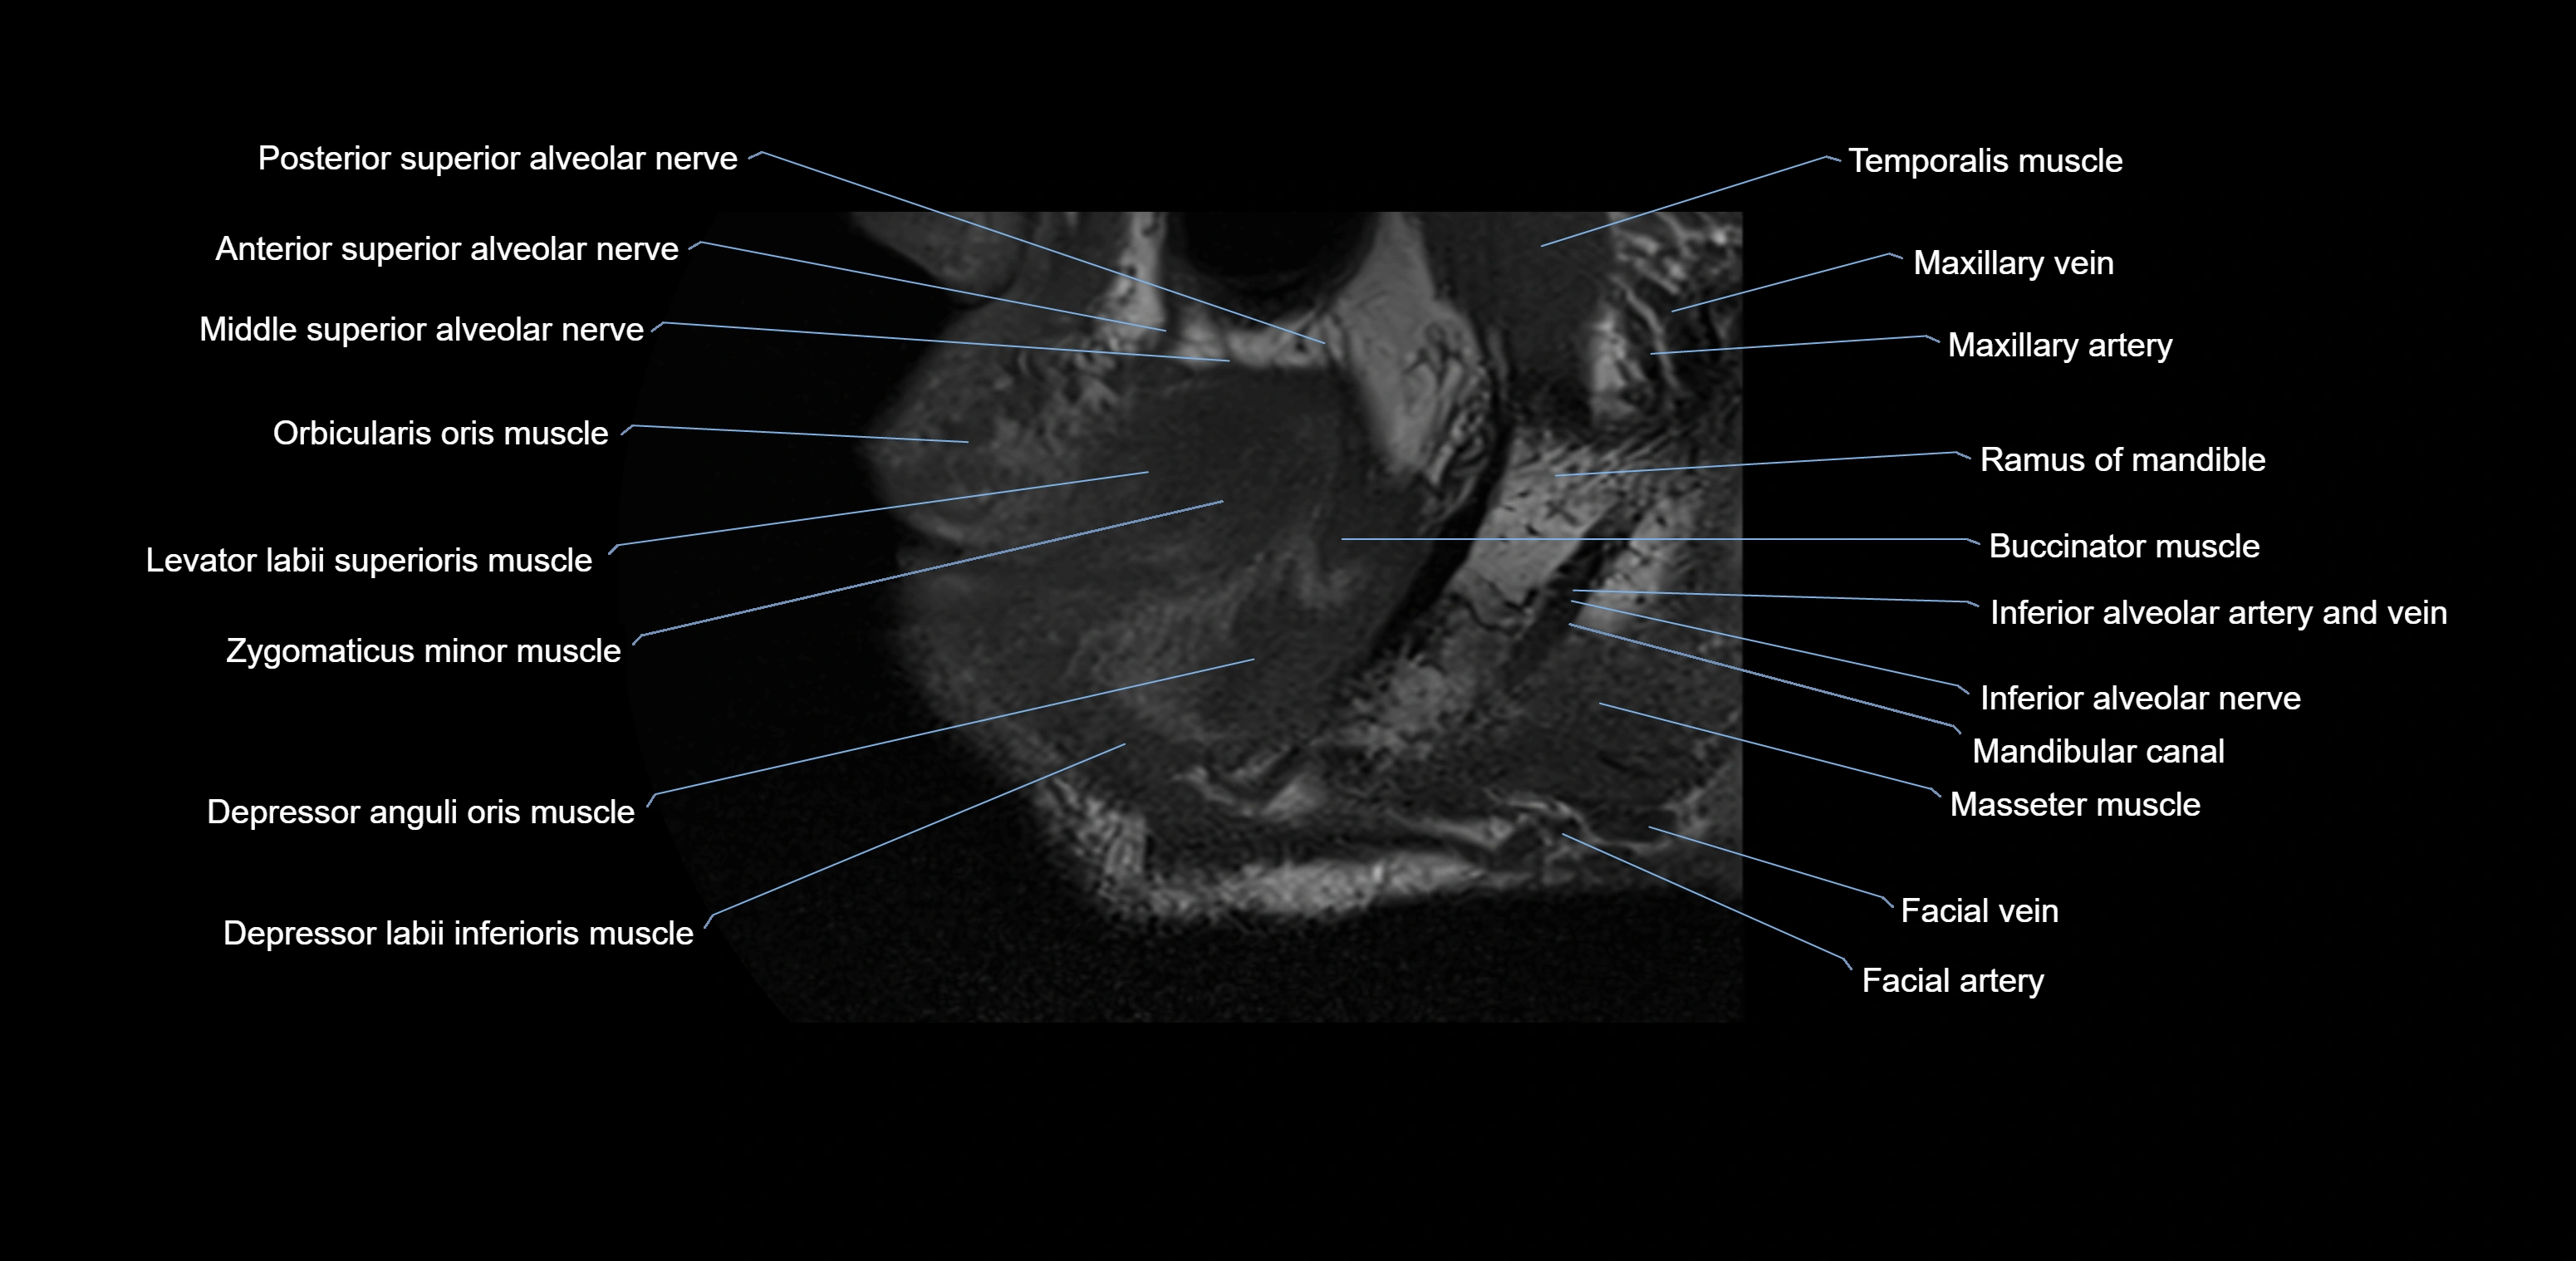

- Anterior superior alveolar nerve

- Middle superior alveolar nerve

- Posterior superior alveolar nerve

- Orbicularis oris muscle

- Levator labii superioris muscle

- Depressor anguli oris muscle

- Depressor labii inferioris muscle

- Buccinator muscle

- Mandibular canal

- Inferior alveolar nerve

- Masseter muscle (Deep part)

- Masseter muscle (Superficial part)

- Ramus of mandible